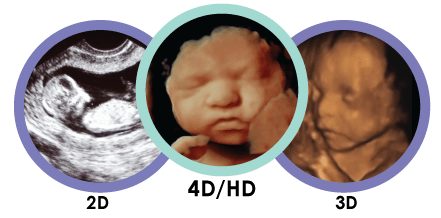

2- سونوگرافی 3 بعدی

بر خلاف سونوگرافی سنتی دو بعدی، سونوگرافی سه بعدی اجازه می دهد تا پزشک عرض، قد و عمق جنین و اندام شما را ببیند. این سونوگرافی می تواند به ویژه در تشخیص مشکلات مشکوک در دوران بارداری مفید باشد.

سونوگرافی سه بعدی با همان روش سونوگرافی استاندارد انجام می شود، اما از پروب و نرم افزار مخصوص برای ایجاد تصویر 3 بعدی استفاده می شود. این سونوگرافی نیاز به آموزش ویژه برای تکنسین دارد، بنابراین ممکن است به طور گسترده ای در دسترس نباشد.

3- سونوگرافی 4 بعدی

سونوگرافی 4 بعدی ممکن است به عنوان یک سونوگرافی 3 بعدی دینامیک نامیده شود. بر خلاف سایر سونوگرافی ها، یک سونوگرافی 4 بعدی یک تصویر متحرک از جنین ایجاد می کند. این سونوگرافی تصویر بهتری از چهره و حرکات کودک ارائه میکند . این سونوگرافی همچنین برجسته تر و سایه ها را بهتر نشان میدهد. این سونوگرافی همانند سونوگرافی های دیگر انجام می شود، اما با تجهیزات خاصی انجام می شود.